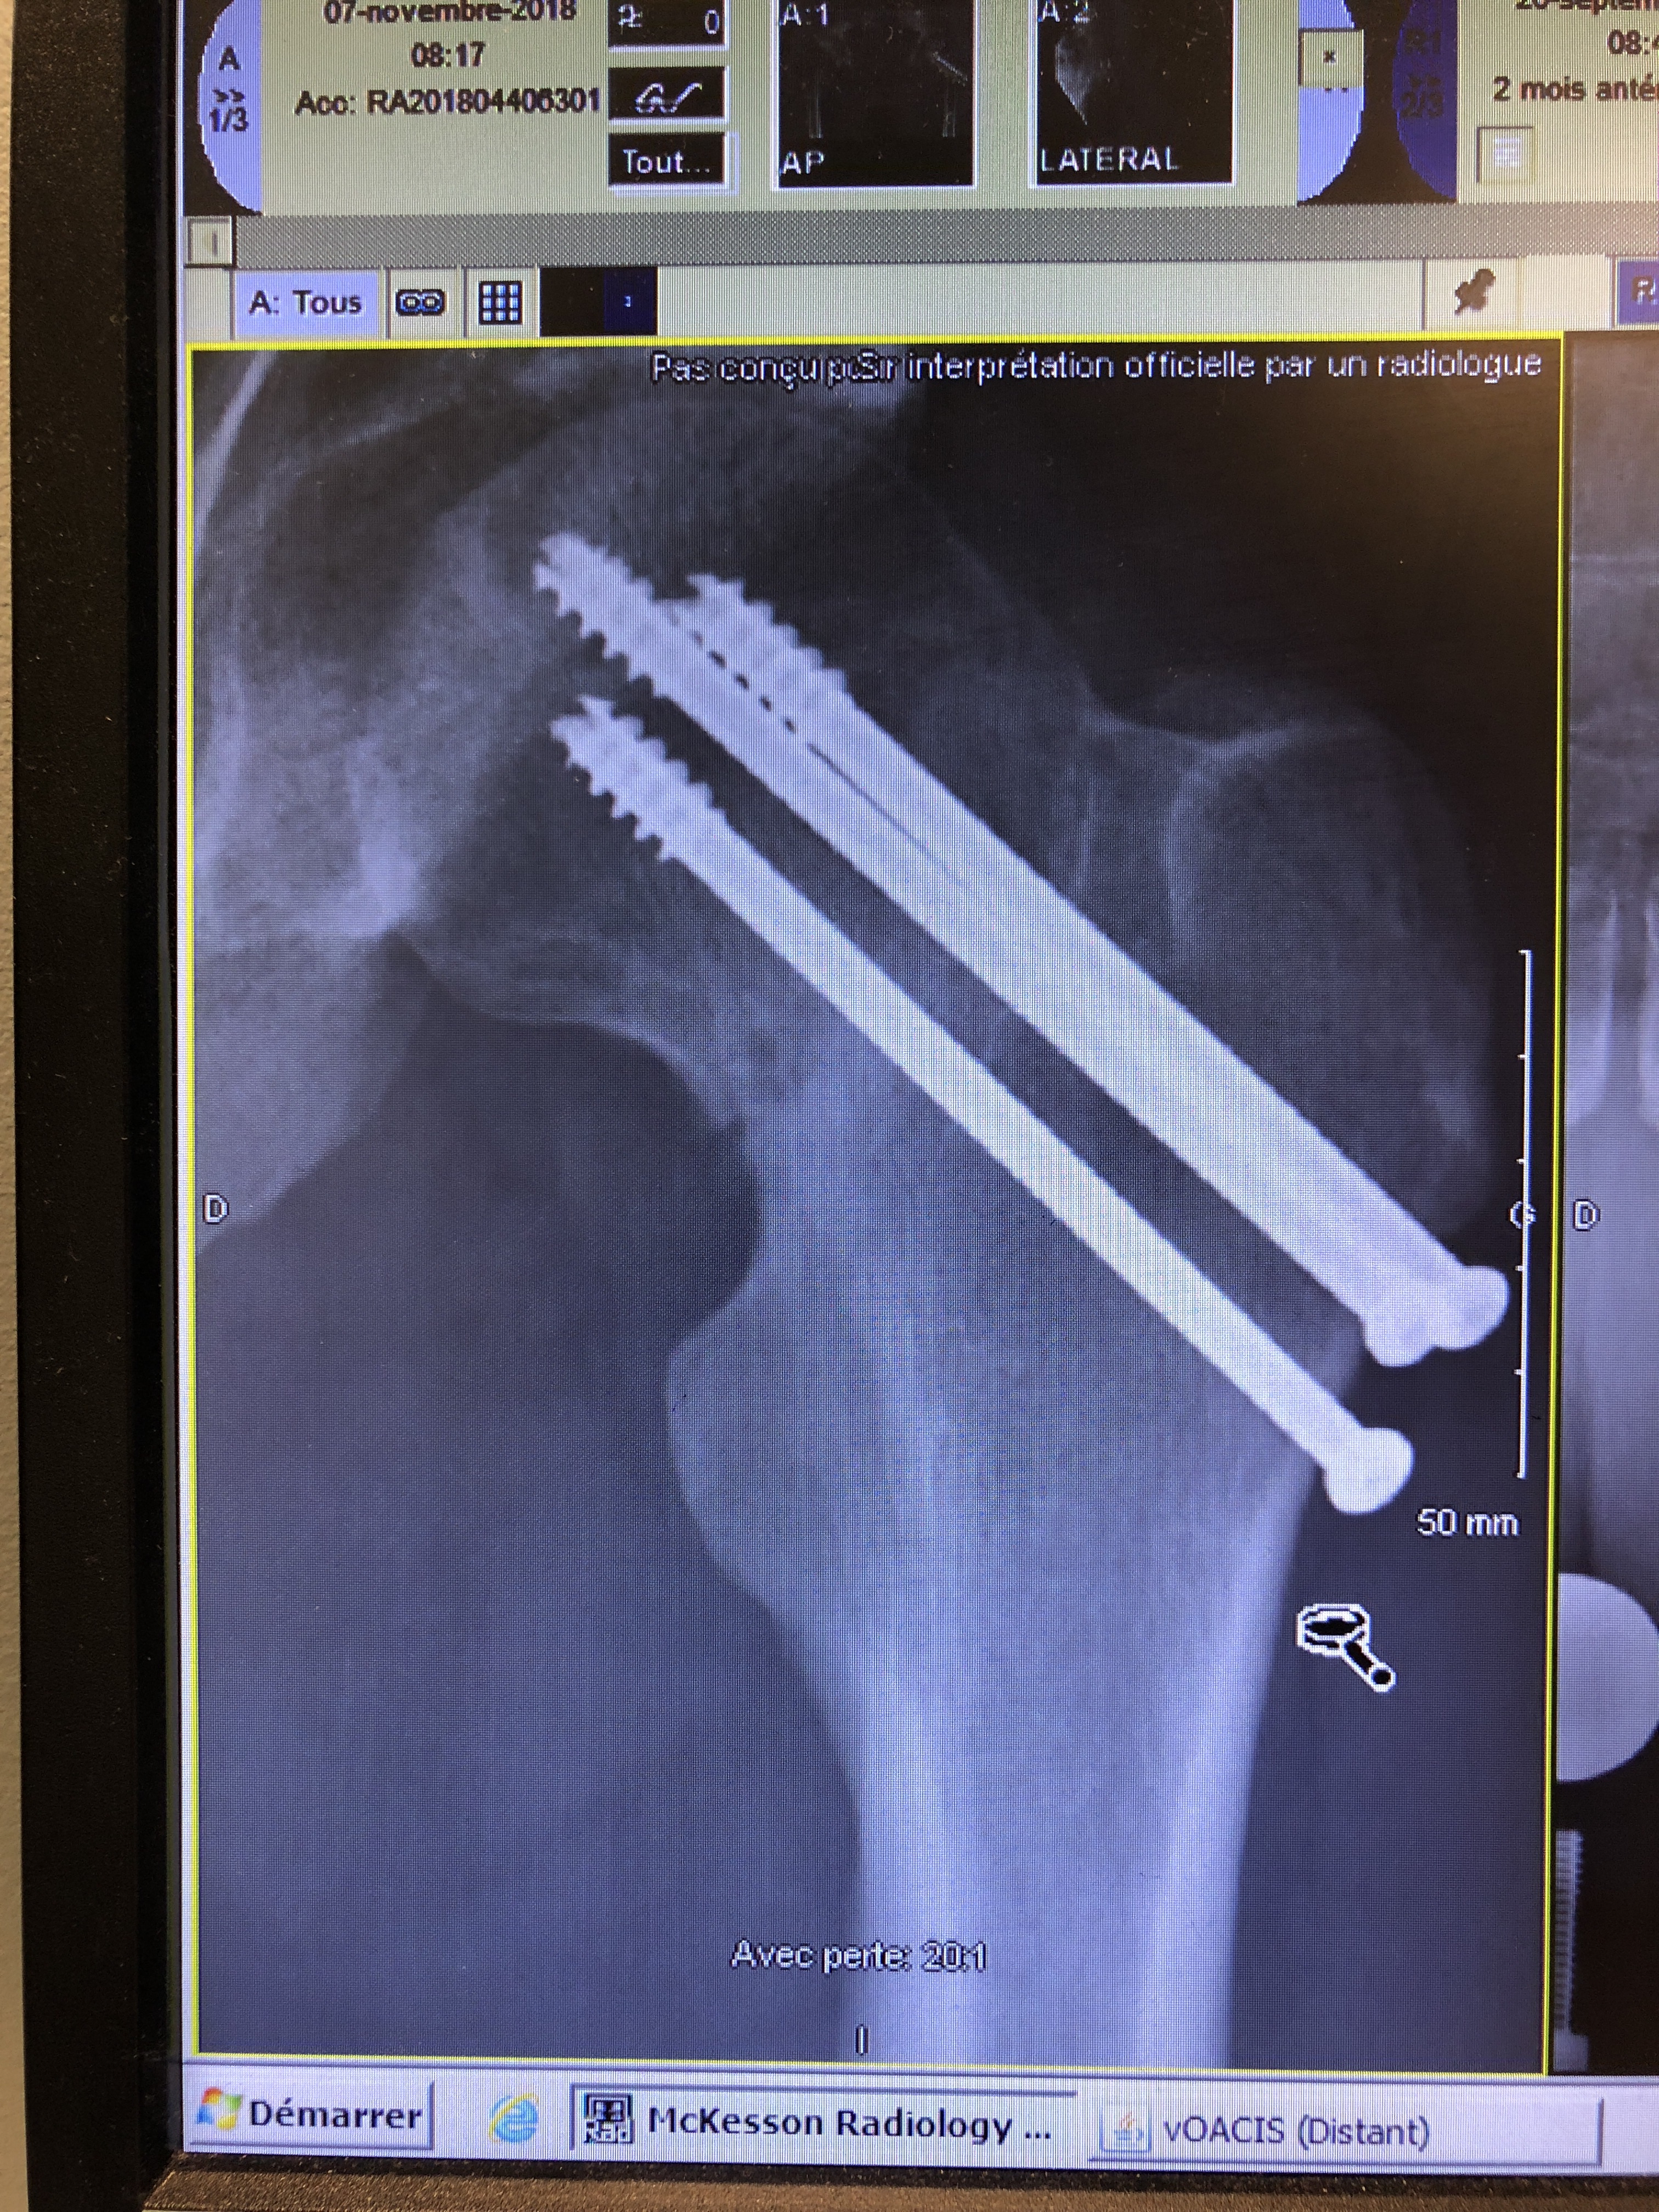

The Knees. The knees start to hurt. My longest ride since last year was seventy-five clicks long. I guess my preparation wasn’t perfect. I put it down to commitment. I have a hard time with self confidence, knowing and owning what I think. I have a hard time finishing things. I usually end up quietly putting them aside, hoping no one notices, hoping I can buy my way out of it later.